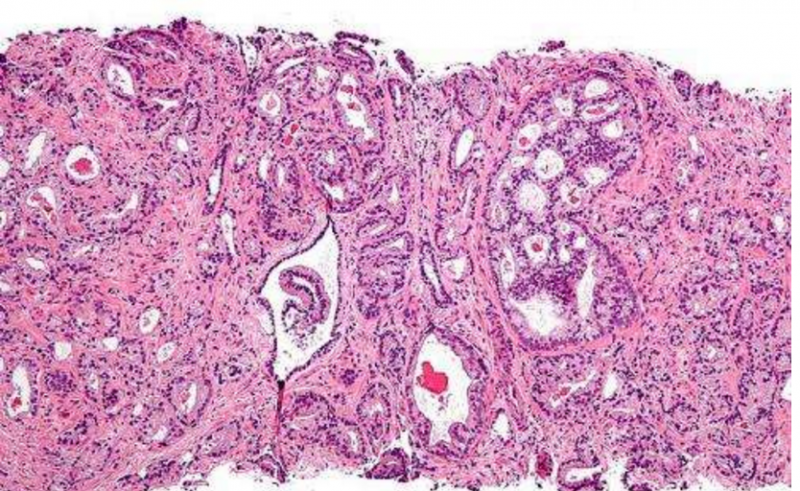

前列腺癌放疗,前列腺癌放射治疗科普前列腺癌是最常见的男性泌尿生殖系统恶性肿瘤之一,发达国家居男性恶性肿瘤发病率首位。2019年国家癌症中心发布的数据显示:前列腺癌发病率居男性恶性肿瘤的第6位,死亡率居第10位。01、前列腺癌可以放疗吗前列腺癌主要治疗方法为手术、放疗、内分泌治疗,因此前列腺癌可以放疗。局限性前列腺癌患者进行根治性手术和放疗可治愈;部分年纪较大